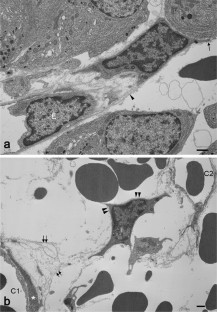

Prolactinomas are the most common tumor of the human pituitary. They result in excessive prolactin secretion and important changes in the vasculature. Pericytes are perivascular cells associated with capillaries and have crucial roles in physiological and pathological neovascularization. We previously reported that pericytes produce type I and III collagens in the anterior pituitary of adult rats. In addition, pituitary pericytes contained well-developed cell organelles and actively synthesized collagens during early postnatal development. However, the characteristics of pericytes in pituitary tumors are unclear. In this study, we used diethylstilbestrol (DES)-treated rats as an animal model of prolactinoma. Using five common pericyte markers, more pericytes were observed in rats treated with DES for 3 months (prolactinoma) compared to the control. Transmission electron microscopy revealed that attached and semidetached pericytes exhibited active cell organelles. Moreover, we identified pericyte migration between capillaries. Although the fine structure of pituitary pericytes was active in prolactinoma, expressions of type I and III collagen mRNAs were greatly diminished. In sum, the characteristics and functions of pericytes were altered in pituitary tumors. This study is the first to clarify fine structural changes of pericytes in rat prolactinomas and improves our understanding of the function of pericytes under pathological conditions.

Fig. 1